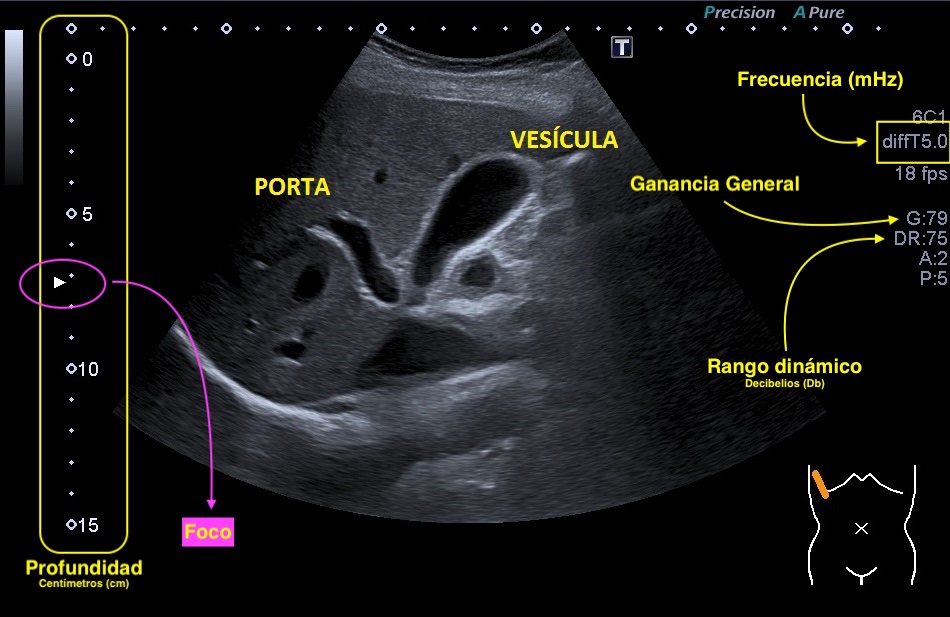

1. Ganancia general: Ajuste que controla el brillo global de la imagen. Normalmente situado en el comando 2D.

2. Ganancia Parcial: Ajuste que controla el brillo de la imagen con una serie de potenciómetros y lo hace en las distintas profundidades de la imagen según la necesidad de cada estudio.

3. Frecuencia: Parámetro técnico que controla la nitidez de la imagen y se expresa en megahercios.

4. Foco: Ajuste ecográfico que no ofrece nitidez en la zona de posición del mismo. Debe estar a la altura del objeto de estudio o una línea inferior.

5. Rango dinámico: Es el ajuste que controla el contraste de la imagen. Se expresa en decibelios.

6. Profundidad: Es el ajuste que tenemos que adaptar al estudio que estemos realizando para no cortar la estructura de interés. Aparece en una escala lateral centimetrada de la imagen.